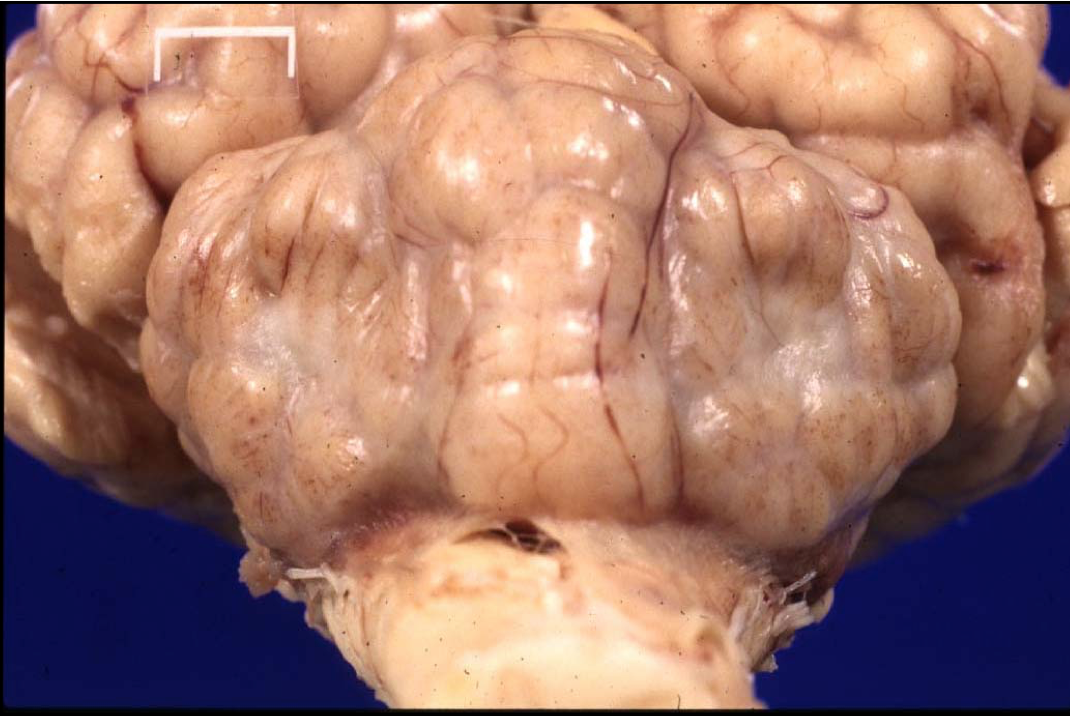

Cerebral meningoencephalitis

DDX:

E.coli

Histophilus

MCF